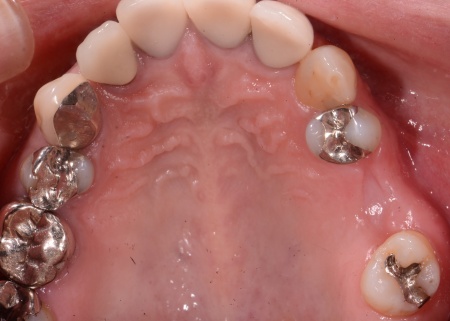

拝見したところ、左上奥歯の歯茎が腫れ、強い痛みがあることが確認されました。

レントゲン撮影による詳しい検査を行ったところ、歯根周辺や歯を支える骨にまで炎症が広がっており、歯を温存することが難しいことがわかりました。

以上のことから、左上奥歯(第1大臼歯)を抜く必要があると診断しました。

すでに強い痛みや腫れが出ていたため、来院当日に左上奥歯(第1大臼歯)を慎重に抜きました。抜歯後は、炎症の改善と骨の回復を待ちます。